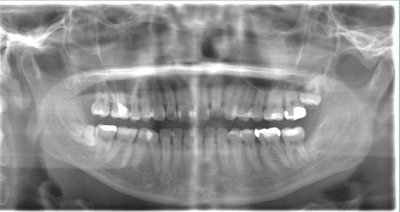

CASE 3

| 年齢・性別 | 20代・男性 |

| 主訴 | 左下親知らず抜きたい |

| 親知らずのはえ方 | 半埋伏 |

| 抜歯期間 | 30分 |

| 抜歯費用 | 約2,500円(保険内) 別途CT撮影で3,000円 |

| 抜歯内容 | 左下の半埋伏親知らず抜歯 |